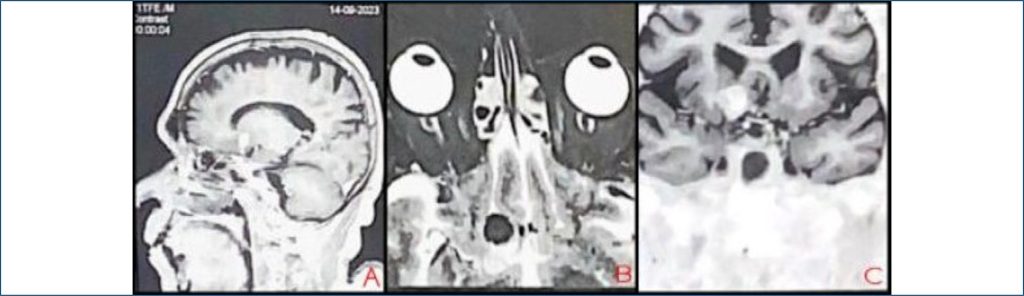

O objetivo deste relato foi demonstrar a importância do exame neuro-oftalmológico, especialmente a avaliação do reflexo pupilar, na identificação de alterações neurológicas em pacientes assintomáticos, evidenciando seu papel crucial na detecção precoce de aneurismas intracranianos, mesmo na ausência de sinais clínicos evidentes. Trata-se de relato de caso observacional, retrospectivo e descritivo de um paciente do sexo masculino, 70 anos, com glaucoma crônico. Durante avaliação oftalmológica de rotina, foi identificado um defeito pupilar aferente relativo no olho direito, levando à solicitação de ressonância magnética craniana e orbital para investigação complementar. A ressonância magnética revelou um aneurisma sacular grande (1,5 x 1,2 x 1,5 cm) na porção comunicante da artéria carótida interna direita, em contato com estruturas cerebrais adjacentes, sem sintomas prévios. O paciente foi encaminhado para acompanhamento neurológico especializado e controle da pressão intraocular. A avaliação neuro-oftalmológica permitiu a detecção precoce de uma lesão potencialmente fatal em paciente assintomático, destacando a importância de exames oftalmológicos regulares e da abordagem interdisciplinar no diagnóstico de condições neurológicas graves.